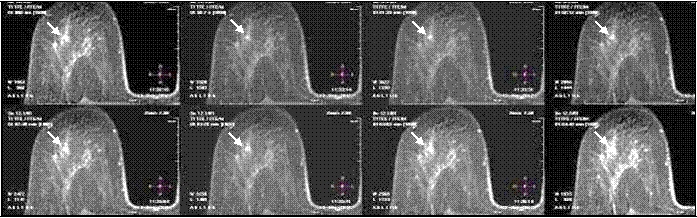

Использованная нами методика МР-маммографии с динамическим контрастированием позволяла оценить процесс накопления КП не только с высоким пространственным, но и временным разрешением (рис. 8). Что было особенно важно для дальнейшей обработки полученных данных – построения параметрических карт и кривых для оценки интенсивности, скорости накопления и сброса КП патологическим очагом.

Рисунок 8 — МР-маммография с контрастированием. Серия динамического изображения. В динамике можно оценить увеличение интенсивности МР-сигнала от образования, указанного стрелкой, связанное с накоплением КП.